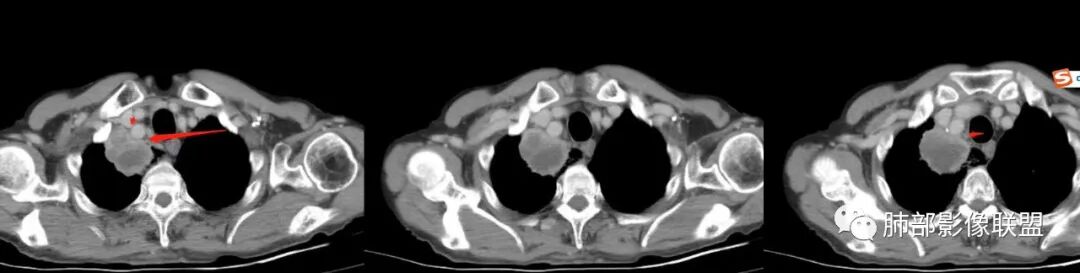

老年人,有高血压、脑梗死、肾结石病史

这次,半月,左胸痛不适,高热:39°C,白细胞、中性粒细胞高

主病灶在右上叶尖段、前段纵隔旁,紧贴胸膜

楔形、边缘膨隆,附近见斑片状、网格状高密度影

支气管近端堵塞,可惜显示的不一定全面

支气管壁还是弥漫增厚

中央坏死明确

整体内壁偏清楚,似乎有些地方欠清,不知道是否厚层所致

整体而言:远侧、内侧壁厚

坏死明显,这类膨隆就不支持生长速度不一致所致,而支持坏死朝周围的压力导致边缘的膨隆

这里倒是符合血管的压迫

与胸膜的关系?分界还算清楚